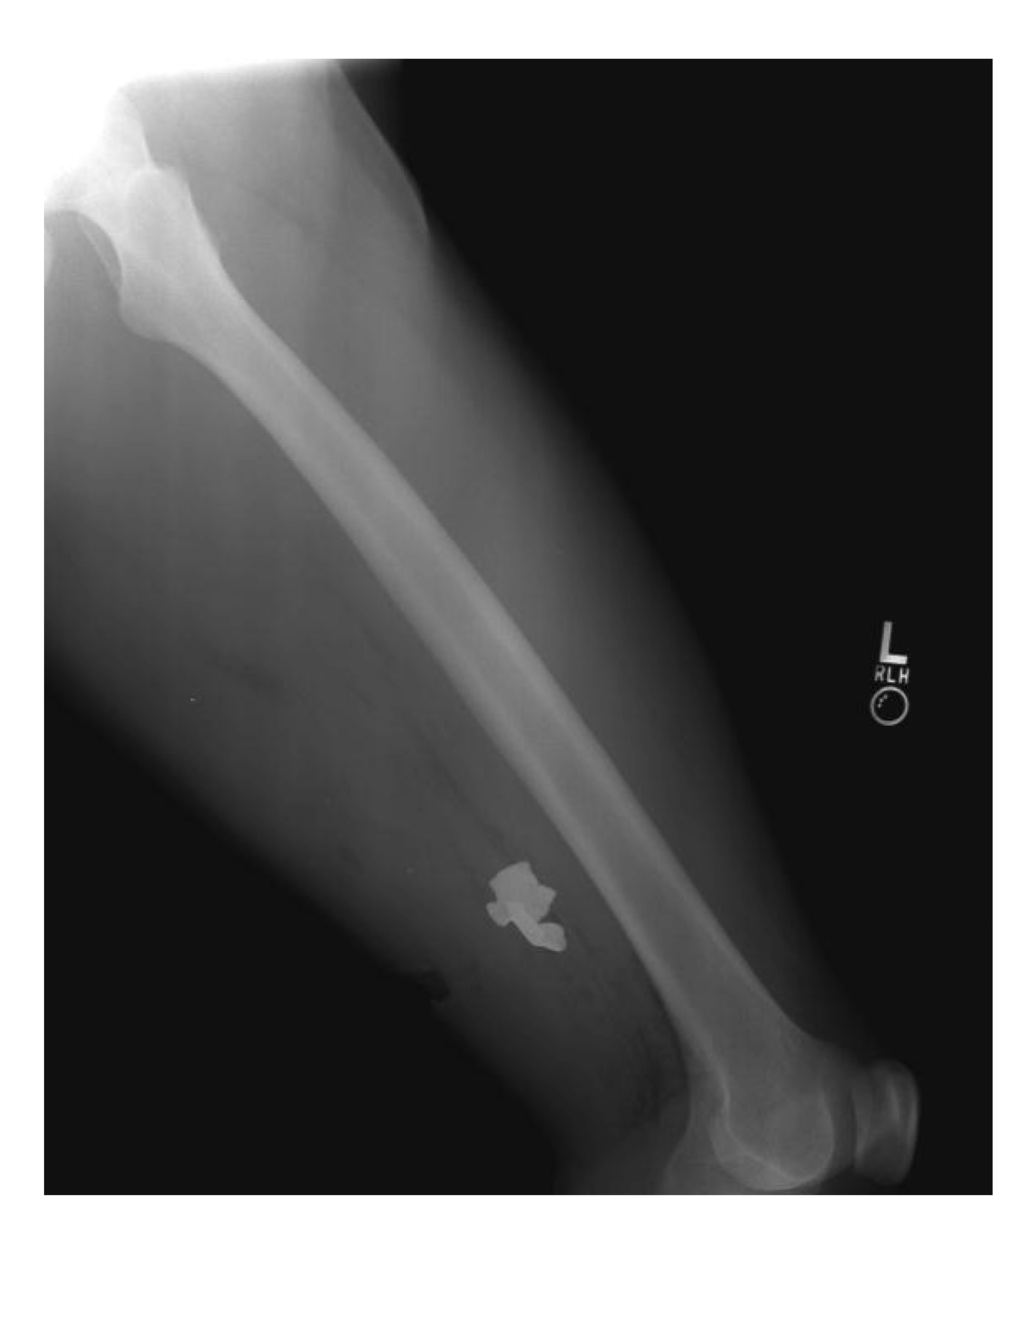

3.2.1. Case Number 1

3.2.3. Case Number 3

3.2.4. Case Number 4